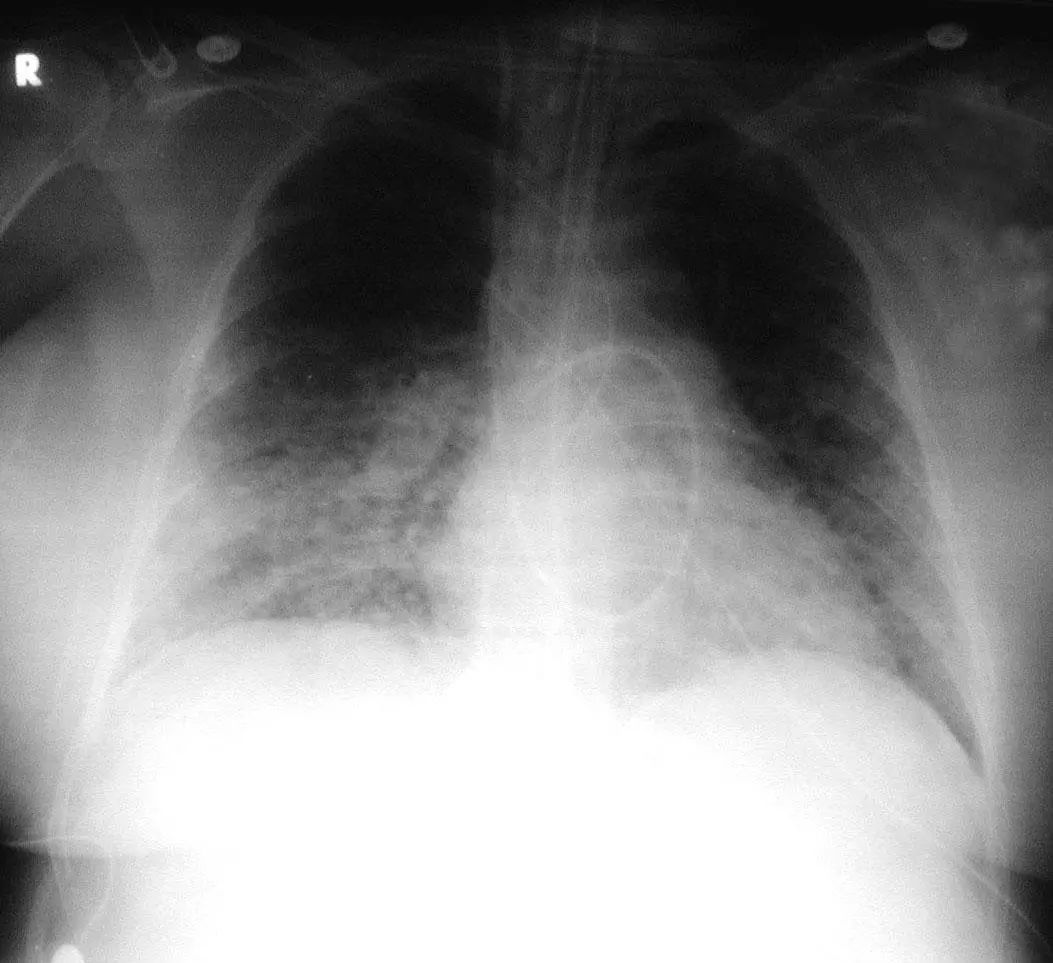

图1.5 40岁肺炎衣原体患者。胸片显示右上、中、下叶多灶性斑片状实变。